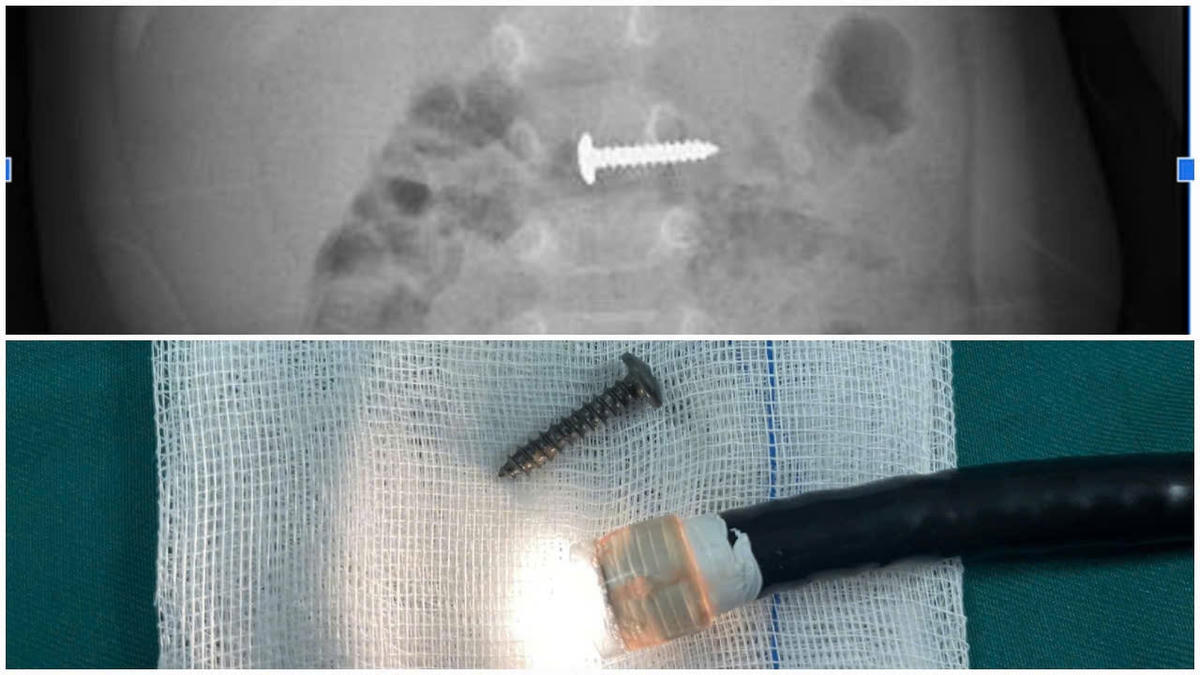

Bệnh nhi được các bác sĩ tại Khoa Ngoại Tổng hợp tiến hành khám và chỉ định chụp X-quang bụng không chuẩn bị thẳng. Kết quả phát hiện dị vật nằm trong đường tiêu hóa, có kích thước 24,15mm.

Ngay khi phát hiện hình ảnh dị vật, các bác sĩ Khoa Ngoại Tổng hợp đã nhanh chóng hội chẩn, phối hợp với Khoa Thăm dò chức năng tiến hành nội soi gắp dị vật thành công.